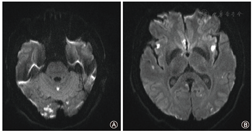

病例2患者男性,52岁。1个月前于我院行房颤导管消融术,主因"寒战、高热2 d,突发胸痛4 h"入院。患者2 d前无明显诱因出现寒战,高热,体温最高40 ℃,自行口服退热药后缓解,4 h前患者突发胸骨后及心前区压榨性疼痛,范围手掌大小,伴四肢麻木、大汗,持续30 min无缓解,遂于当地医院急诊就诊,心电图示Ⅱ、Ⅲ、aVF、V2~V6导联ST段抬高0.5~1.3 mV。实验室检查:肌钙蛋白0.077 µg/L,白细胞计数(13.52×109/L)及中性粒细胞(0.930)升高,高敏C反应蛋白100.27 mg/L,考虑"急性心肌梗死",然而急诊行冠状动脉造影未见异常,术后复查心电图未见明显异常。术后6 h患者再发寒战、高热,体温39.1 ℃,予甲泼尼龙抗炎、莫西沙星抗感染治疗后体温恢复正常,术后18 h患者出现胸闷、心悸,伴大汗,伴意识淡漠,血压80/60 mmHg;心电图示:心房扑动,Ⅱ、Ⅲ、aVF及V2~V6导联ST段抬高。当晚通过网上求助联系我院主管医生,嘱继续禁食水、抗感染治疗,维持血流动力学稳定,同时迅速转往我院。次日凌晨4点半患者转入我院后紧急完善左心房CTA及头颅核磁共振成像检查,弥散加权成像(diffusion weighted imaging,DWI )序列示胼胝体体部、双侧小脑、双侧额颞顶枕叶多发片状新鲜脑梗死(图2)。左心房CTA示纵隔内仅见单个可疑气体影,但脾脏出现新发梗死灶(图3)。经多学科会诊后,考虑"左心房食管瘘"可能性大,急诊行开胸探查术,术中可见左房后壁近左肺静脉处2.0 cm×1.5 cm裂口,以牛心包补片修补裂口后继续探查,发现食管在左下肺静脉上缘附近与心包致密粘连。分离食管和心包后见食管壁及黏膜缺口长约3 cm,缝合黏膜及食管肌层。术后予呼吸机辅助通气治疗,16 h后恢复意识,术后第2天拔除气管插管。患者血培养示:以革兰氏阳性菌为主的混合感染,予亚胺培南联合左奥硝唑抗感染后未再出现寒战、发热。术后第10天复查食管造影,口服造影剂后见食管中下段局部管壁不规则,管壁尚柔软,管腔通畅,未见造影剂外漏。遂逐步恢复患者自主进食。术后第26天患者康复出院,未遗留神经系统症状。